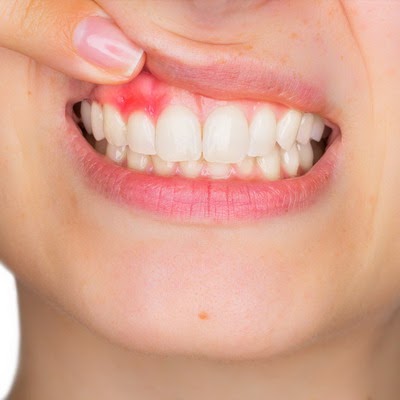

- отечность десны в области грануляции;

При нагноении гранулемы присоединяются симптомы интоксикации с тошнотой, гипертермией, недомоганием, головной болью. При надавливании возможно подтекание гнойного экссудата. Боль может иррадиировать от зуба-провокатора по челюстному ряду, отдавать в виски. При нагноении вероятно увеличение подчелюстных лимфоузлов. Длительное бессимптомное течение инфекционного процесса приводит к его отграничению, формированию плотной капсульной оболочки с некротическим компонентом.